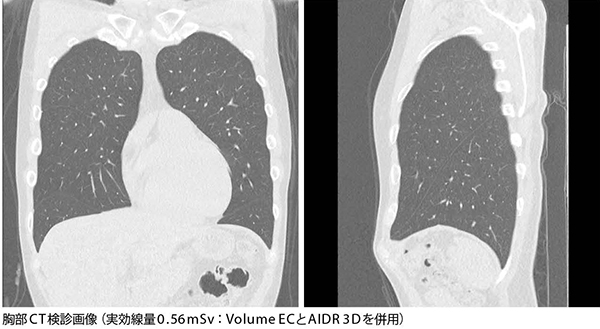

■Aquilion PRIME/Focus Editionによる胸部低線量撮影画像

[AIDR 3Dを使用した胸部、腹部での低線量撮影]

低線量撮影の画像の評価について緑川部長は、「診断にはまったく問題ありません。腹部と胸部では撮影条件を変えており、特に肺については被ばくを下げるため低電圧撮影を行っています」と説明する。胸部CT撮影条件は、Volume ECとAIDR 3D(SD30)を使用し、低線量での検査を行っている。松井技師は低線量撮影について、「どこまで線量を下げられるか、稼働前に東芝の担当者とも相談して、AIDR 3Dのレベルによる画像の違いを緑川部長にも確認してもらい、プロトコールを決定しました」と説明する。CTでは0.5mmで撮影し、5mm再構成、コロナル画像も提供している。緑川部長は、「CTの本体でコロナル画像まで作成できることで、時間の短縮や手間を省くことができました。コロナル画像は受診者への説明にも利用しています」と述べる。